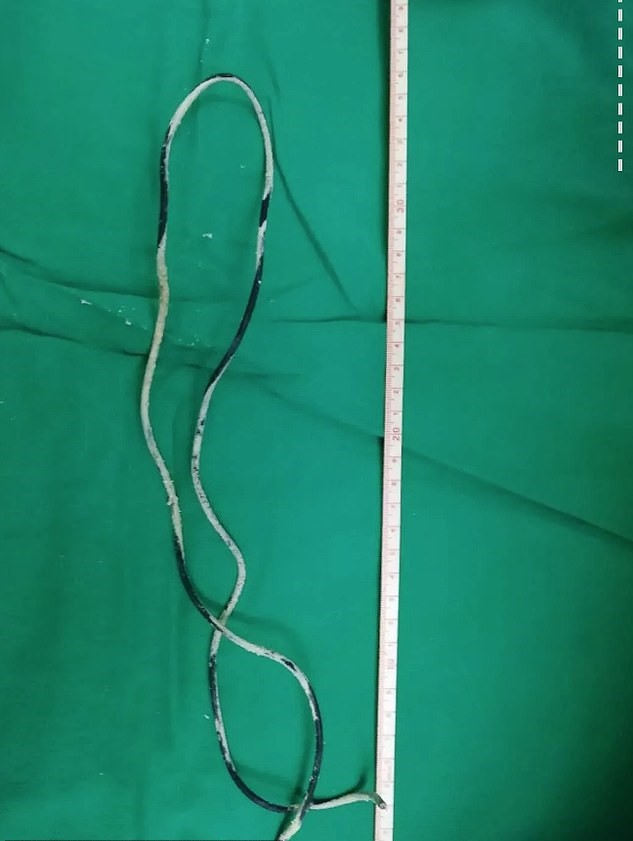

El cable medía más de medio metro.

Los médicos se sorprendieron al descubrir el cordón enredado dentro de la vejiga del niño en una radiografía.

Los médicos programaron inmediatamente a Xiao He para que se sometiera a la cirugía y sacaron el largo cable de su uretra.

El cirujano jefe que dirigió la operación, el Dr. Cai Chongyue, dijo: “No imaginaba que se pudiera insertar un cable tan largo a través de la uretra.”